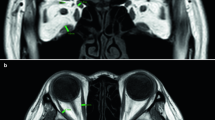

Image fusion of CT and scintigraphic data showing diffuse Octreotide uptake in the lower limbs of a patient with TAO. Octreotide uptake represents inflammatory activity. Taken from [49]. Each reconstruction plane is labeled in the upper left corner of the image. The right lower image is an anatomical reconstruction of the surface of the leg.

On clinical grounds, thyroid disease can be found to be associated with musculoskeletal components such as with polymyositis [35, 36], eosinophilic fasciitis [37], as well as with myalgia and swelling of the calves and fasciitis [31]. Recent investigations have found an increased peripheral glucose utilization, i.e. 18F-fluorodeoxyglucose uptake in the muscles of patients with Graves' disease [46]. Increased peripheral glucose metabolism can signalize inflammatory changes [47]. Finally, indirect evidence on the presence of inflammation in muscles of TAO patients, e.g. neck muscles [50] and shank [49] (Figure 12), can be seen through the use of radioactive labeled octreotide, a somatostatin analog which can depict immunological or inflammatory sites in TAO [95]. Alterations of neck muscles can be viewed as being directly related to postural changes [96–99]. While previous investigations in TAO have focused on the EOM, it should be recalled that there are large differences in muscle mass between the EOM and the limb muscles. EOM have a volume of 3–5 ml [100, 101], while the muscle mass of the legs together with abdominal muscle can amount to 15–20 kg [102, 103]. It follows, that biochemical markers of inflammation such as GAGs [19, 20] are more likely to come from peripheral muscles. The postural changes we describe here correspond to an eccentric muscle action of peripheral muscles. The consequences of eccentric action will be discussed in the following section.

6) Scintigraphic imaging data in relation to the model

We would like to highlight the diagnostic possibilities of Nuclear Medicine in the context of the model. Figure 15 shows the diagnostic capabilities of combined PET-CT scanners (in this example SIEMENS, Erlangen, Germany). The fused image, i.e. superposed PET and CT whole body images, shows metabolic activation of the left lateral shank while at the same time the right ankle also shows increased metabolic activity. We interpret this image in 2 ways. In the first place it shows the anatomical localization of the changes we describe. In the second place it demonstrates the research capabilities of whole body PET-CT imaging in musculoskeletal studies with emphasis put on "whole body analysis". The image was kindly provided by Dr. David Townsend, University of Tennessee [165].

Metabolic imaging using whole body 18F-Fluorodeoxyglucose PET and CT. Note the metabolic activity on the lateral side of the left lower limb as well as on the right ankle. The area around the ankle corresponds to the Shen mai acupuncture point which has been evaluated in our study. Shank muscles are commonly more active in locomotion. The image was provided courteously by Dr David Townsend, University of Tennessee [165].